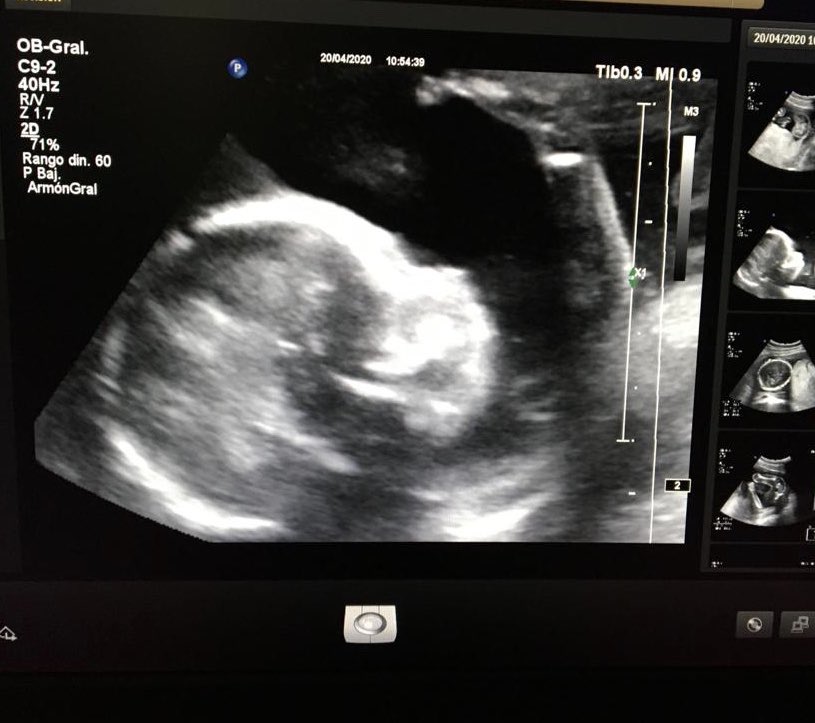

#infertilpandy Eco de la semana 20 superada! Os presento a mi niña ☺️ estamos muy contentos, viviendo un sueño, ojalá pronto todas estéis en mi misma situación. La placenta baja, eso si, tengo que hacer seguimiento en 6 semanas a ver si sube 🙏. Un abrazo,fuerza y animo a todas💙